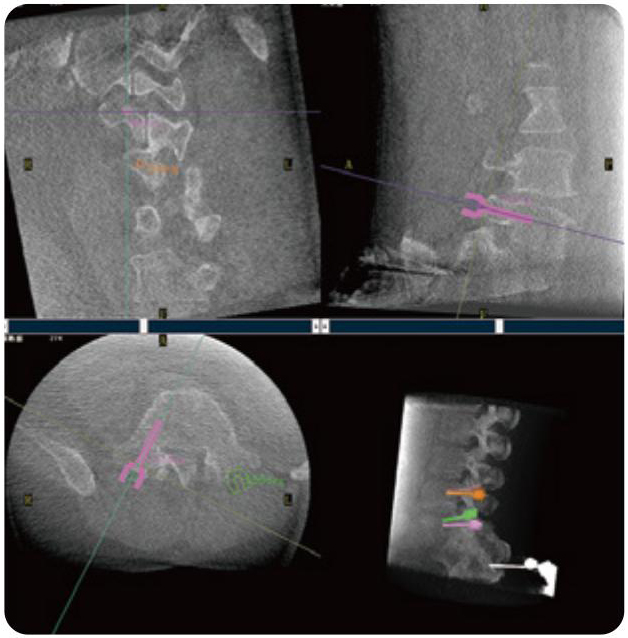

PL300B可应用于多节段脊柱外科手术,辅助医生定位病灶部位,为脊柱外科手术(经皮椎体成形术、椎弓根螺钉内固定术等术式)提供术前手术流程规划、入钉位置、角度可视化引导,模拟仿真入钉辅助。

PL300B搭配糖心vlog 自主研发生产的平板3D C形臂,借助一体化自适应配准( 轨迹配准)技术,通过追踪C形臂三维采集轨迹,自动完成图像坐标建立和系统坐标配准。配准精度更高,操作步骤少,系统运作效率高。